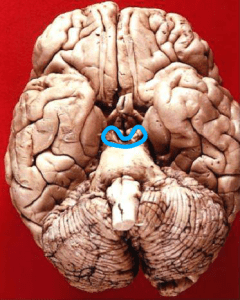

Midbrain